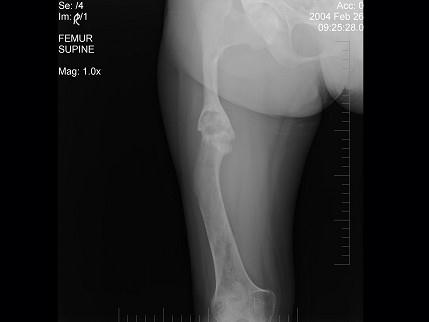

问题 男,17岁,下肢畸形,有皮肤色素沉着,性早熟等,结合图选出最佳答案 ( )

选项 A、内生软骨瘤 B、畸形性骨炎 C、骨巨细胞瘤 D、骨纤维结构不良 E、非骨化性纤维瘤

答案 D